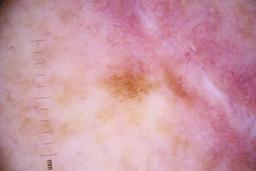

ISIC_4077341

- Challenge 2020: Training

- IP_1969685 IL_9238622

Clinical

| Field | Value |

|---|---|

| acquisition_day | 1 |

| age_approx | 50 |

| anatom_site_1 | Trunk |

| anatom_site_2 | Anterior trunk |

| concomitant_biopsy | False |

| dermoscopic_type | contact non-polarized |

| diagnosis_1 | Benign |

| diagnosis_confirm_type | serial imaging showing no change |

| family_hx_mm | False |

| image_type | dermoscopic |

| lesion_id | IL_9238622 |

| patient_id | IP_1969685 |

| personal_hx_mm | True |

| sex | male |